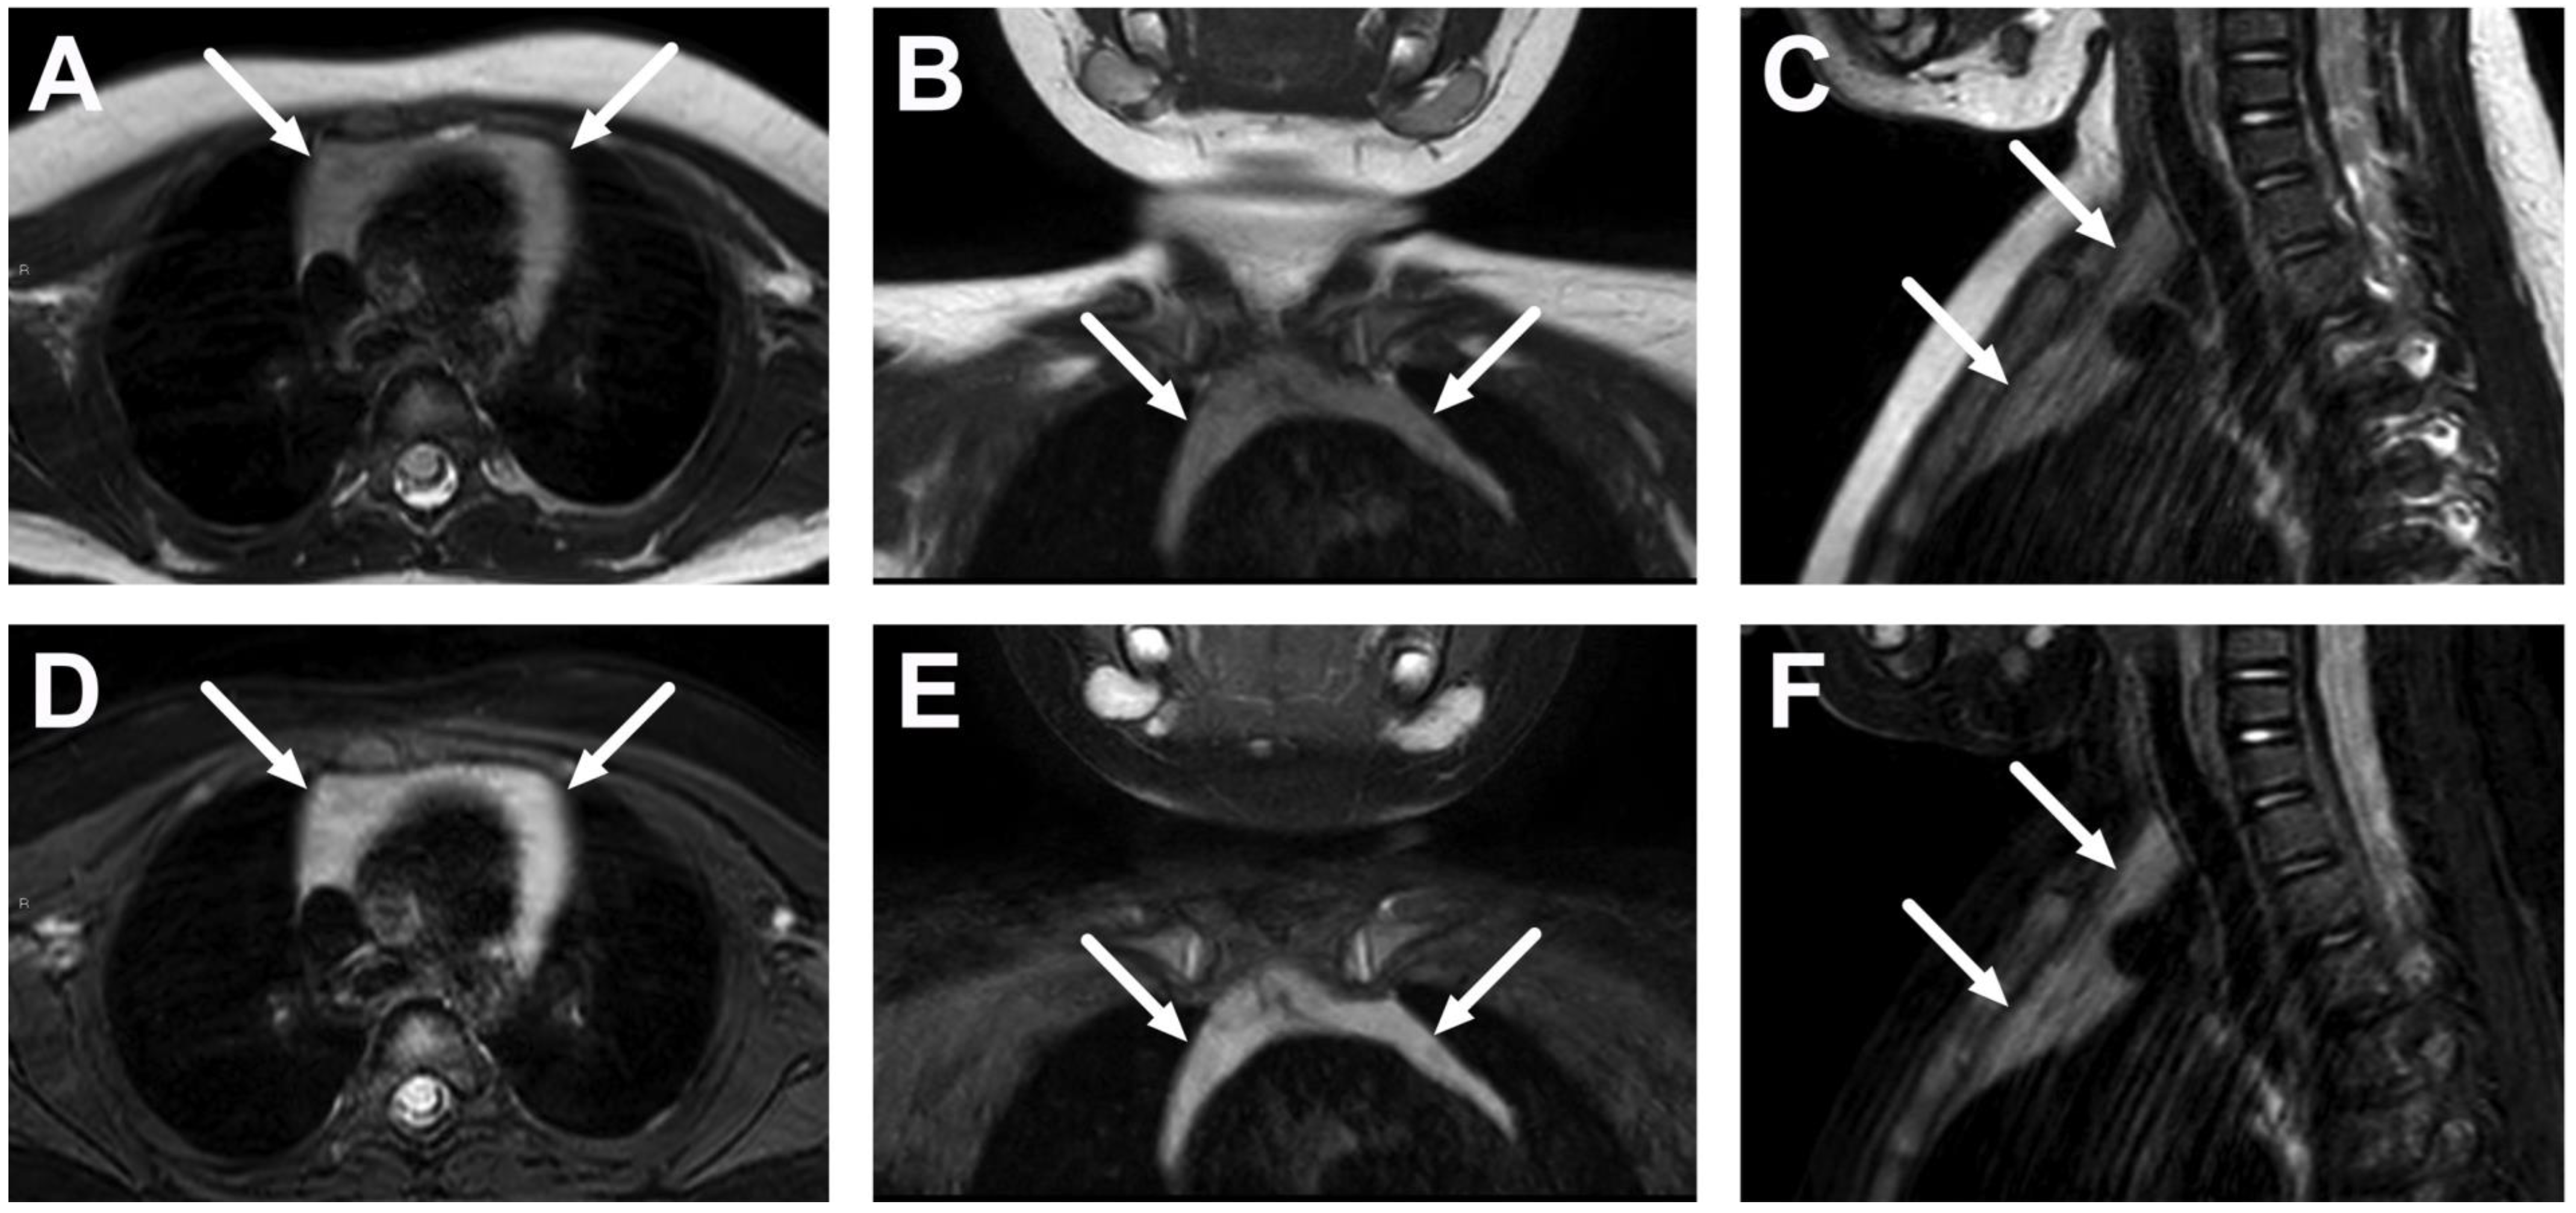

| Complications | Whole protocol | Abscess extending to multiple deep neck spaces, mediastinis, venous thrombosis, and airway compromise. | Detection of potentially life-threatening conditions. | Magnetic resonance angiography (MRA) or CECT may be needed to diagnose venous thrombosis; defining airway compromise is difficult. |